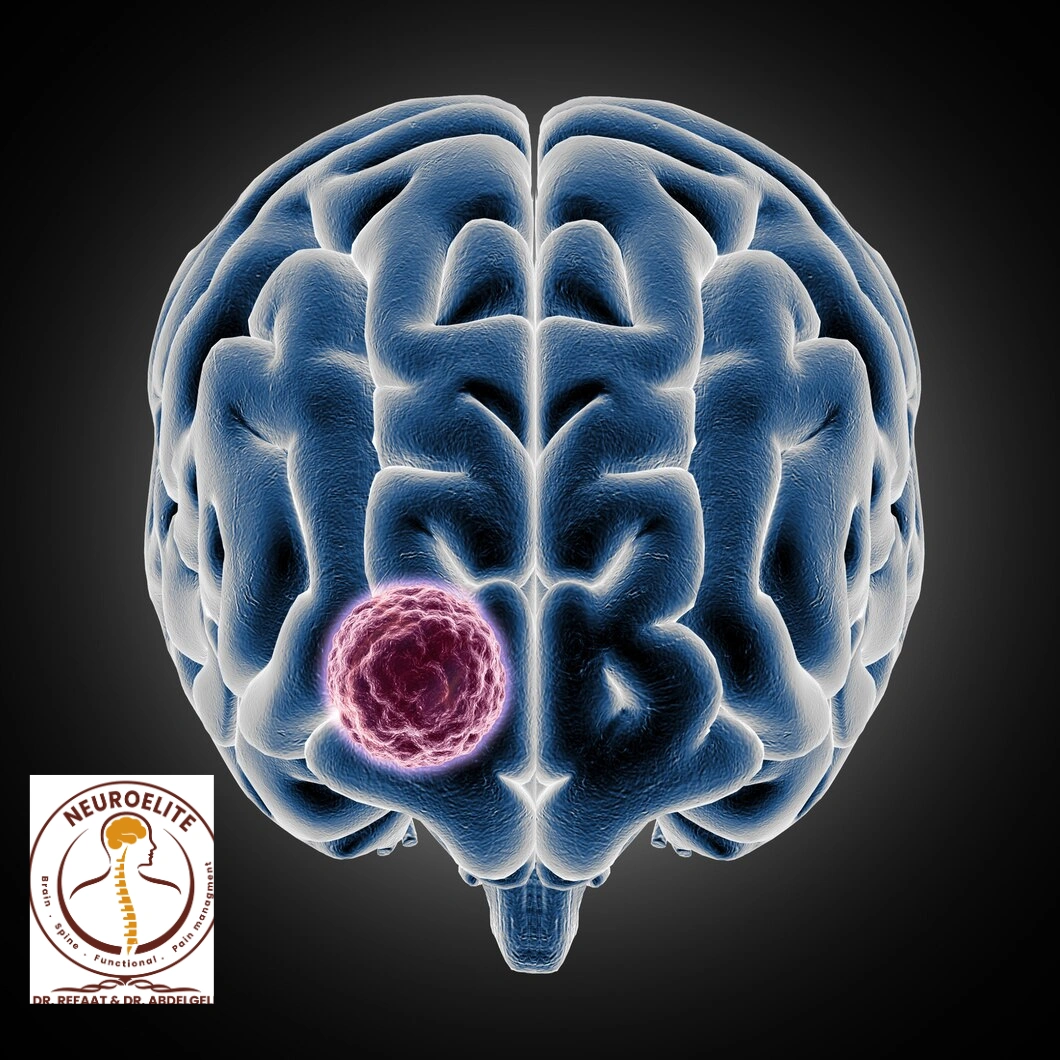

أورام المخ

أورام المخ قد تكون حميدة أو خبيثة، لكنها في كلتا الحالتين قد تؤثر على وظائف الدماغ بسبب الضغط على الأنسجة المحيطة. تختلف خطورتها حسب نوعها ومكانها وسرعة نموها. يعتمد العلاج على الجراحة أو الإشعاع أو الأدوية الحديثة. في مركز نيرو ايليت، يتم وضع خطة علاج فردية لكل حالة لضمان أفضل نتائج ممكنة.

ما هو سرطان المخ؟

سرطان المخ هو نمو غير طبيعي وغير منضبط للخلايا داخل أنسجة الدماغ أو الأغشية المحيطة به. يمكن أن يكون هذا النمو خبيثًا (سرطانيًا) أو حميدًا، إلا أن كلا النوعين قد يشكل خطرًا بسبب الضغط على أجزاء الدماغ الحساسة.